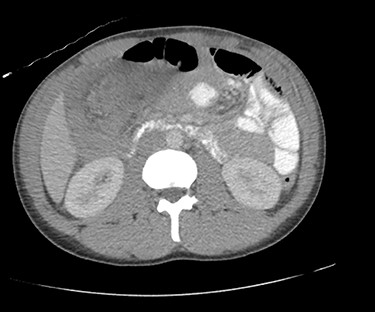

Due to diagnostic uncertainty, the patient underwent a computed tomography (CT) of the abdomen and pelvis with intravenous and oral contrast, which demonstrated ileo-colic intussusception, a distended ileum and no other features of bowel obstruction. Coronal and axial views of the CT scan showing the ileocolic intussusception are displayed in Figs 1 and 2, respectively.

CT of the abdomen and pelvis with coronal view showing ileo-colic intussusception.